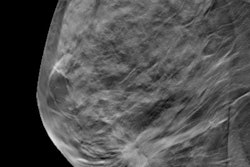

The researchers said that diagnostic mammography compression views may still be needed because asymmetries and focal asymmetries can represent undercompressed breast tissue. In the current study, they wanted to compare the performance of diagnostic evaluation using breast ultrasound alone versus ultrasound and additional mammographic views for noncalcified findings recalled from screening mammography with DBT.

The team looked at data collected between 2017 and 2019 from 430 recalled noncalcified lesions in 399 women with an average age of 60. Ultrasound alone was performed on 306 of the total lesions, while ultrasound with diagnostic mammography was performed on the other 124 lesions.